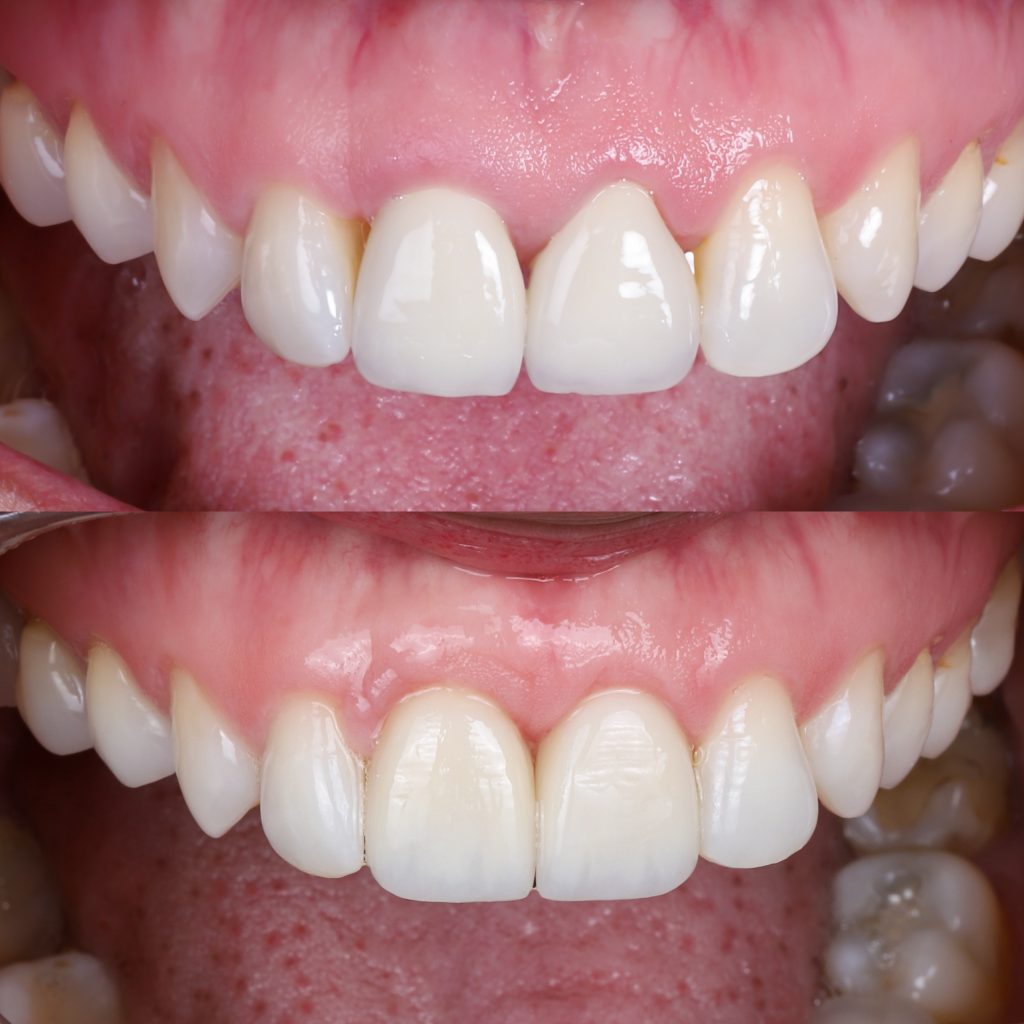

Fotos de encías retraídas antes y después

En las fotos de encías retraídas antes y después del tratamiento puede verse la diferencia:

una encía más gruesa, rosada y firme, y una raíz que vuelve a quedar protegida.

En Alejandro Prieto Dental, documentamos los casos con imágenes clínicas (previo consentimiento del paciente) para mostrar los resultados reales obtenidos con el injerto de encía.

Estos tratamientos logran una mejora estética y funcional visible en pocas semanas.

Encías retraídas: antes y después del tratamiento

El cambio tras el tratamiento es evidente: las raíces dejan de verse, el color se unifica y la sonrisa recupera su armonía.

Las fotos de encías retraídas antes y después muestran una mejora notable tanto estética como funcional.